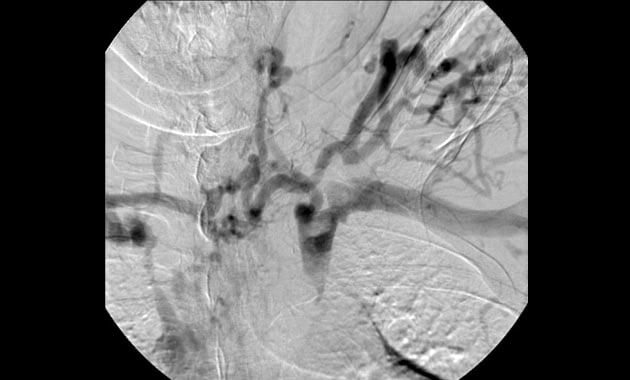

Portal Hypertension

- Conditions: Portal hypertension, esophageal varices, gastric varices, variceal bleeding, ascites, portal vein thrombosis, Budd-Chiari syndrome

- Services: Transjugular intrahepatic portosystemic shunt (TIPS), Balloon-assisted retrograde transvenous obliteration (BRTO), portal vein recanalization, paracentesis, abdominal PleurX placement